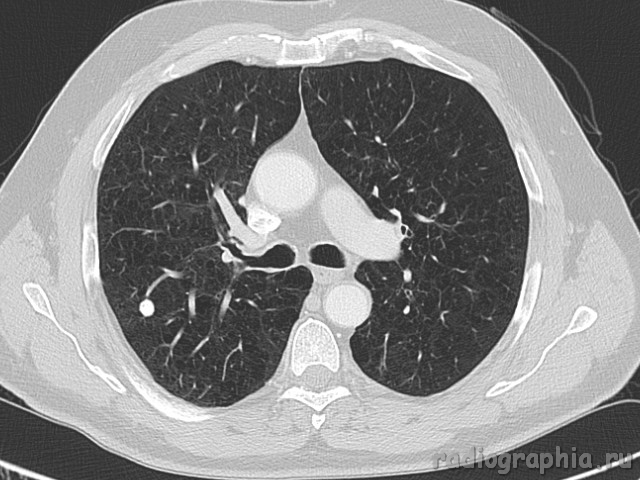

Одиночный узел правого лёгкого.

На рутинном снимке ОГК, был выявлен одиночный узел; по протоколу выполнили КТ. Какое было бы ваше заключение; и как бы Вы поступили если у вас нет возможности выполнять КТ?